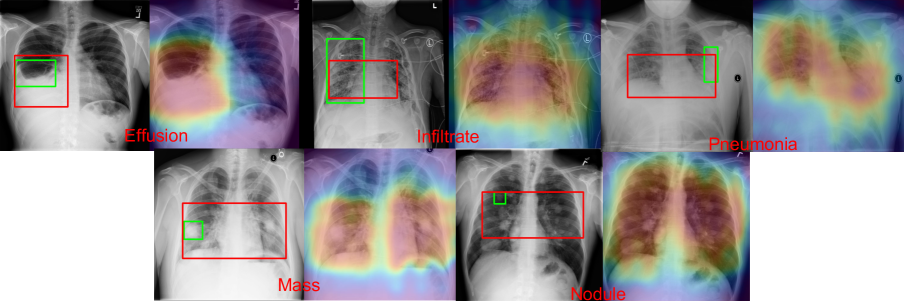

We presents 5 ambiguous cases on 5 diseases in Figure 6, which represents bias in localization annotations that leads to lower IoU score. In the case of ”Effusion”, the annotation outlined the liquid-lung boundary. Instead, our network includes the full liquid rinsed area. In the cases of ”Infiltration” and ”Pneumonia” that spread both lungs, the ground truth annotations only includes single lung, whereas our network captures both lungs. For cases like ”Mass” and ”Nodule”, the ground truth bounding box only highlights one of many instances of ”Mass” and ”Nodule”, but our localization highlights all instances.

Refer to caption

Figure 6: This shows 5 ambiguous cases on 5 diseases where bounding annotations are bias. The input image is shown on the right, with two bounding boxes labels: green is the provided ground truth and red is our localized bounding boxes. The class-pooling output heatmap is shown on the right. The red bounding boxes are generated by applying a naive thresholding.